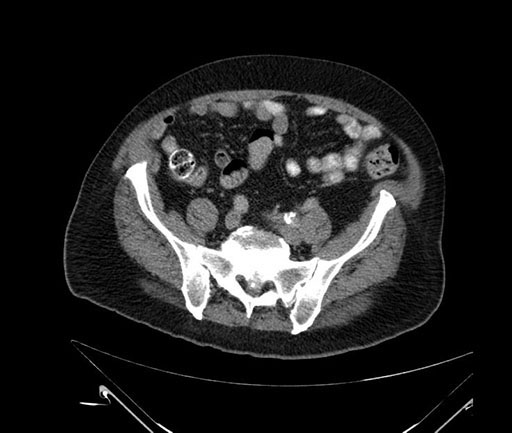

Whipple (pancreaticoduodenectomy) [case 7]

Imaging Analysis

Look through the patient's CT scan to identify any areas of concern for the necessary procedure.

Based on your CT findings, which issue(s) would give reason for "planned slowing down moment(s)" in this case?

Considering a standard Whipple procedure, what step(s) of the operation would you do differently in this case?